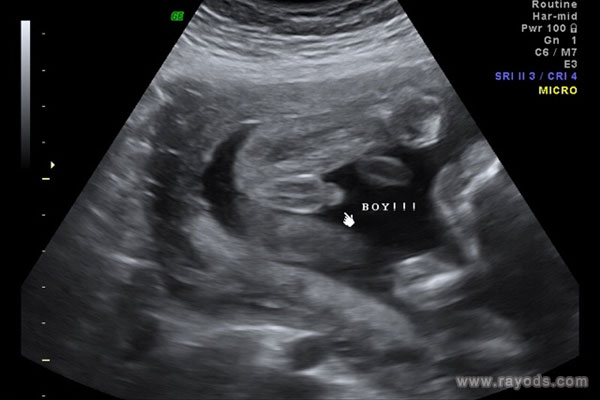

b超可以精确测量宝宝身体的各个数据,看器官发育是否正常等,但现在b超看胎儿似乎已经演变成了可以看性别的方法和途径。据了解,网上有不少关于b超看男女的方法,看起来似乎有理有据,有孕妈称b超时胎儿两腿间有圆圆的东西,都称这是宝宝生殖器,那这是男孩还是女孩呢?

b超胎儿两腿间有圆圆的东西

根据很多医生的解释称,如果胎儿双腿间有圆球的话,通常都是怀男孩的特征。当然,这需要在一个合理的孕周才可以准确判断,通常胎儿在22周之后,男胎女胎的生殖器官都已经发育完全了。这个时候B超可以看到圆圆的一个球,但是不能说就一定是怀的男孩,也可能是女孩。

很多宝妈都认为,如果胎儿两腿间有圆圆的东西和类似于小JJ的话,就可以认为是男孩。但B超检查时因为胎儿小JJ太小,很多时候都是看不清楚或者看不到的。因此,胎儿两腿间有圆圆的东西我们可以判定为是男胎宝宝的睾丸发育出来了,也可能是女胎宝宝的大***发育出来了。所以说,胎儿两腿间有圆圆的东西不一定是就是男孩,也可能是女孩哦。